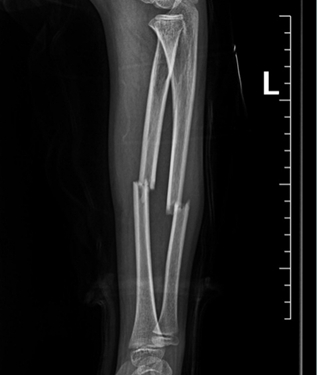

11岁的小豪在学校不慎摔倒,当左前臂剧烈疼痛,不能活动,被紧急送往我院急诊科。结合病史、体征及影像学表现,骨科张栋医师诊断患儿为左前臂尺桡骨双骨折,断端错位,亟需住院手术治疗。

术前,针对该患儿,骨科开展了详细的术前讨论。骨科顾军主任指出,儿童骨折不是成人缩小版,治疗方案不能照搬成人。对于儿童前臂尺桡骨双骨折,传统手法复位石膏固定的保守治疗方法,存在复位不满意、复位失败、骨折再移位等可能,远期会影响儿童前臂旋转功能。而钢板内固定,需要较大的切口,手术创伤大,并发症多,同时会在手臂上留下较长的疤痕,影响外观。微创弹性髓内钉固定术具有创伤小,痛苦少,恢复快等优点,成为此次病例的首选治疗方案。

完善术前准备后,在麻醉科的配合下,周欣、冯晓军副主任医师为患儿实施了左尺桡骨骨折闭合复位弹性髓内钉内固定术。利用手臂上2个仅1cm的小切口就顺利完成了手术。术后,患儿复查X线,效果良好,患者家属对此感到满意,感谢连连。